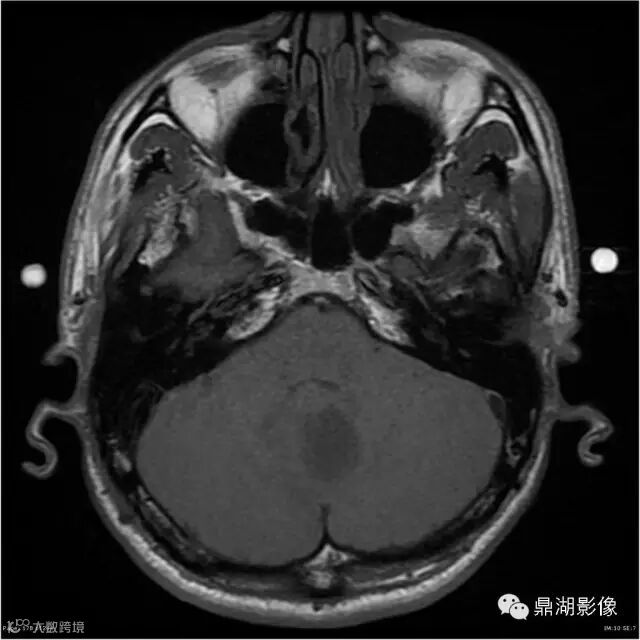

患者男,53岁,头痛、视乳头水肿伴双下肢无力。

影像:可见一个约43 x 36 x 31mm的从小脑蚓部延伸而来的占位,T1WI、T2WI呈高低混杂信号,病灶周边见流空血管影及水肿带,增强病灶明显强化,中心见无明显坏死区,它紧靠左小脑幕上。第四脑室受压变窄,室管膜水肿,可见脑桥及延脑扁桃体进入枕骨大孔。

本例为一例实质性血管母细胞瘤。实性血管母细胞瘤CT平扫示病灶呈等或高密度,增强后可见明显强化。MRI平扫通常病灶很不均质,T1呈稍低信号为主的较混杂信号,T2呈等、高信号,DWI通常呈低信号或等信号。文献报道,实性血管母细胞瘤较典型的表现为瘤内及瘤周扩张的流空血管影,瘤周中、重度水肿。因此,小脑半球区的单发肿块伴流空血管影,周围大片水肿以及增强后肿块明显强化"形态规则"边界清楚,此时应将实性血管母细胞瘤考虑在内。